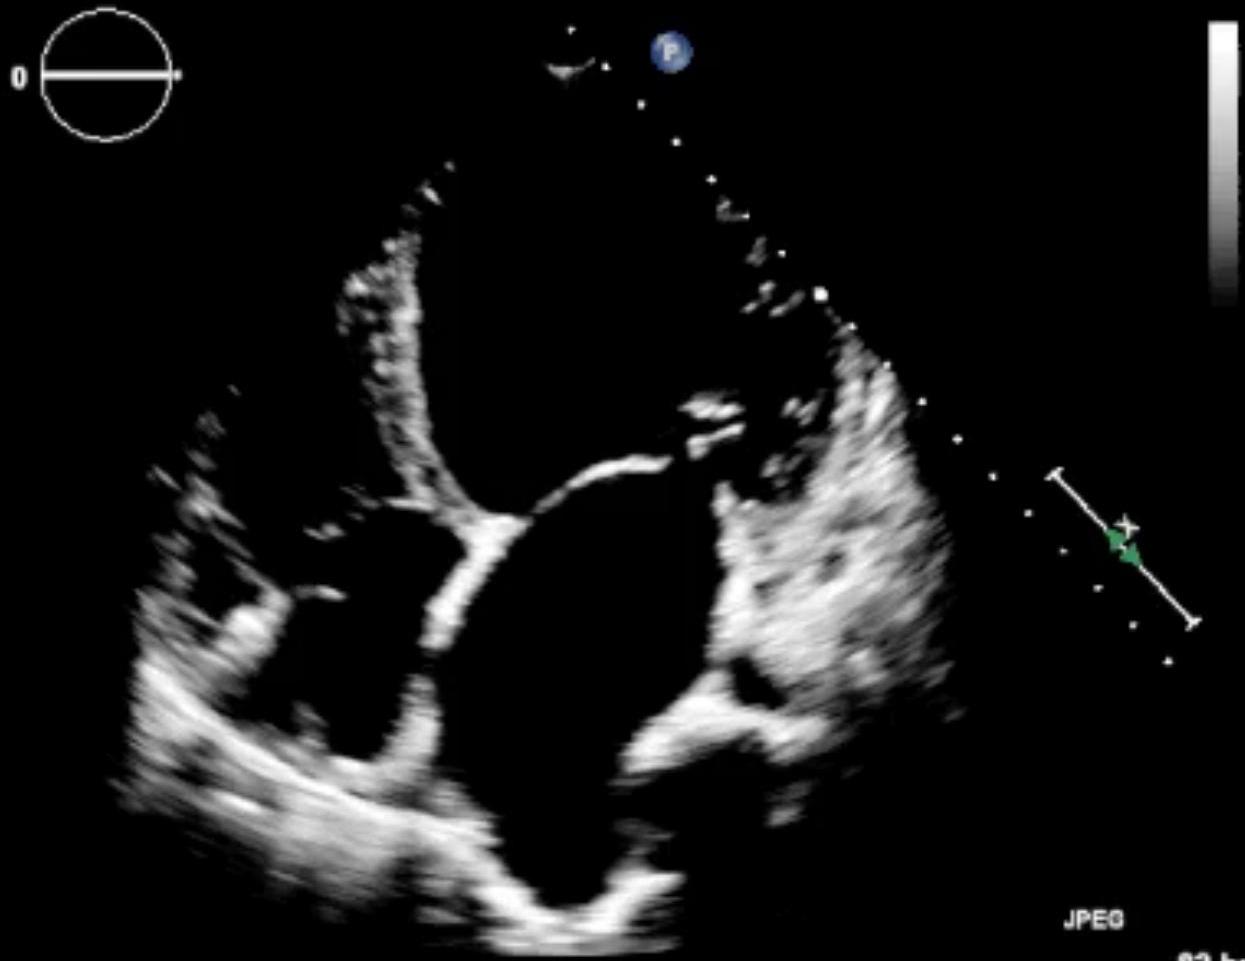

Echocardiography (EF reduced to 20%):

Tamponade: